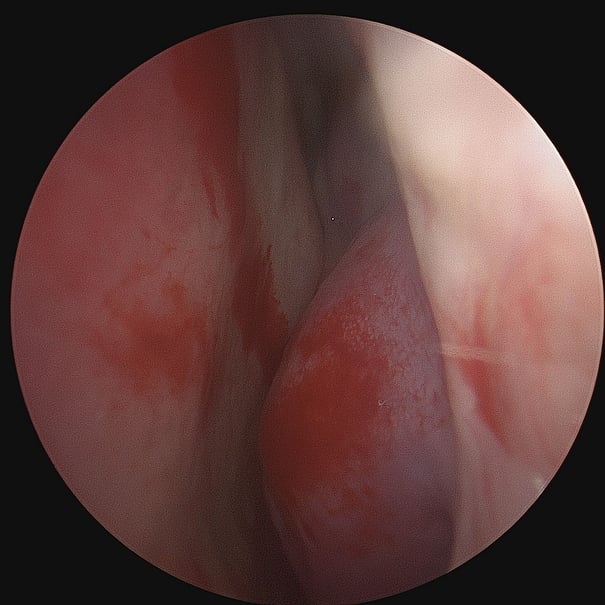

Enlarged Nasal Turbinates (Turbinate Hypertrophy)

Turbinate enlargement refers to the condition where the nasal turbinates become swollen or enlarged. This enlargement can obstruct airflow through the nose, leading to symptoms such as nasal congestion, difficulty breathing and sometimes even snoring . They can also secrete large amounts of mucus.

Some of the causes of turbinate enlargement are allergic rhinitis (hay fever , vasomotor (non-allergic) rhinitis, chronic sinusitis, nasal polyps , abnormal growth of the central turbinate, deviated nasal septum or environmental factors like dry air, irritants, pollutants, or changes in temperature. Turbinate enlargement can also be congenital with very large turbinates running in the family.

This condition can be diagnosed with a thorough examination of the nose to assess for nasal obstruction and signs of inflammation. A nasal endoscopy may be required combined with CT scans to assess the severity of any structural abnormalities or chronic sinusitis. In some cases, turbinate enlargement can be medically managed by use of steroid sprays, antihistamines, decongestants or saline nasal irrigation, along with some lifestyle changes like using a humidifier and minimising exposure to allergens. Otherwise, surgical options may have to be considered. Various techniques effectively reduce their size, like turbinoplasty that has evolved into minimally invasive procedures like Minimally Invasive Powered Endoscopic Turbinate Reduction (MIPET), or use of coblation; septoplasty or sinus surgery (FESS), whereby sinus drainage and ventilation are improved especially in cases where chronic sinusitis is the cause.